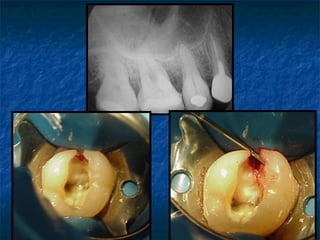

3. Conometría

   Comprueba la posición del cono de

gutapercha seleccionado

   Además confirma si la selección de ese

cono de gutapercha fue la adecuada.

•Longitud

•calibre   1. Arruga en forma de “S” en

extremo apical : CALIBRE       Conometría

SELECCIONADO ES MENOR QUE

EL ADECUADO

a presión

•Resistencia a la tracción

tug-back

   En los dientes con varios conductos

después de insertados los conos se

harán las rx mesio y disto radial

Radiografía           Rx postoperatoria       Rx postoperatoria

preoperatoria de 24   inmediata orto radial   inmediata mesio

angulada

4.- CONDESACION O DE PENACHO:

Con las radiografías se comprueba si la

obturación ha quedado correcta, principalmente

en el tercio apical, llegando a un lugar deseado

sin sobrepasar el límite ni dejar espacios muertos

subcondensados.